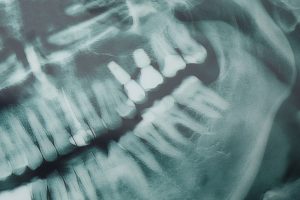

Consultation and imaging

Initial visits include exam, digital photos and a CBCT scan to map bone and sinus anatomy. Your dentist reviews options, timing (immediate vs delayed), and costs.

Upper jaw bone tends to be softer. Clinicians may choose wider or longer implants, different surface treatments, or angled placements to increase stability. Implant choice is based on CBCT imaging and the planned final restoration.